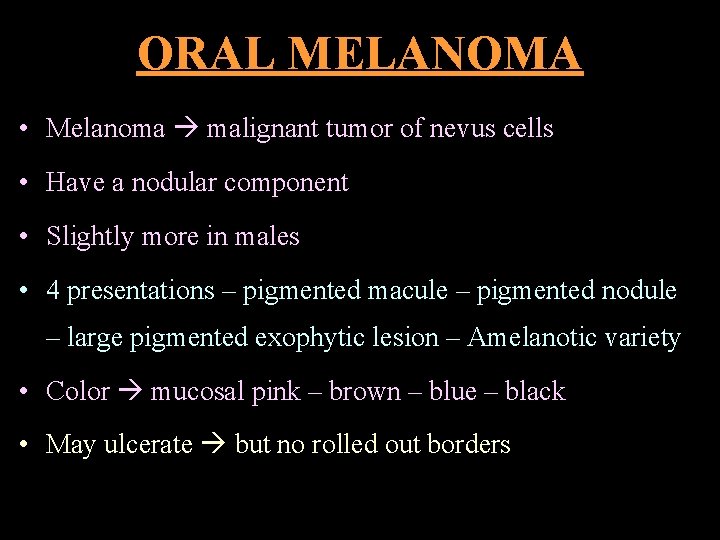

ORAL MELANOMA • Melanoma malignant tumor of nevus cells • Have a nodular component • Slightly more in males • 4 presentations – pigmented macule – pigmented nodule – large pigmented exophytic lesion – Amelanotic variety • Color mucosal pink – brown – blue – black • May ulcerate but no rolled out borders

• Rate of growth slow • Vertical phase rapid • Usually painless • Rapid infiltration fixed to underlying tissues • Spread lymphatic & hematogenous routes • Many develop from nevi

ORAL MELANOMA A – asymmetry C – color variation B – border irregularity D – diameter > 6 mm D/D: • Oral melanotic macule • Amalgam tattoo • Nevus • Focal hemosiderin deposit